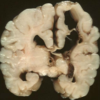

Name the pathologic process.

Hydrocephalus

Name the pathologic process.

Hydrocephalus

Name the pathologic process.

Hydrocephalus